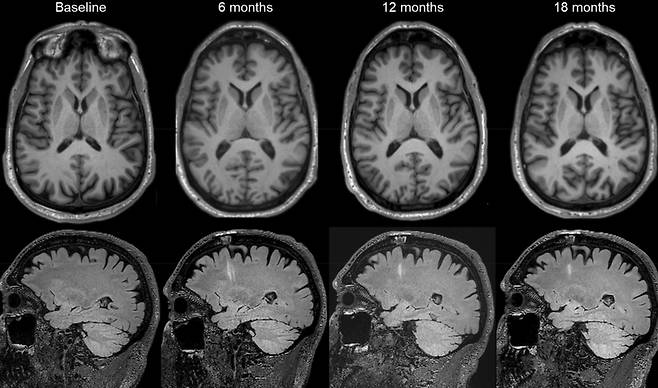

이식한 세포는 뇌에서 도파민을 만드는 신경세포가 됐다. 연구진이 환자들을 18개월 추적 관찰한 결과 별다른 부작용은 발견되지 않았다. 배아줄기세포는 분화(分化) 능력이 뛰어나 자칫하면 종양이 될 수 있다. 다행히 그런 문제는 없었다고 연구진은 밝혔다.

줄기세포 이식 시술은 파킨슨병 증상도 줄였다. 연구진은 환자들을 대상으로 근육 경직, 떨림, 운동 속도 저하같은 파킨슨병 증상을 평가했다. 그 결과 저용량·고용량 그룹 모두 파킨슨병 증상이 호전됐다. 특히 고용량 그룹은 파킨슨병 증상이 50% 감소한 것으로 나타났다. 줄기세포를 많이 이식할수록 치료 효과가 좋다는 것을 의미한다.